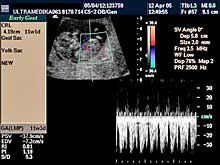

- Prva procena posteljične cirkuacije Broandband - CD

Primenjena tehnika:

- Broadband 2D,

- harmonik mod,

- Sono CT,

- XRes,

- 3D Sono CT,

- CPA.